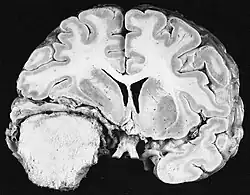

Glioblastoma

Os tumores de células gliais mais comuns e malignos são os glioblastomas. Consistem em uma massa heterogênea de células de astrocitoma pouco diferenciadas principalmente em adultos. Geralmente ocorrem nos hemisférios cerebrais, mais raramente no tronco cerebral ou na medula espinhal. Exceto em casos muito raros, como todos os tumores cerebrais, eles não se estendem além das estruturas do sistema nervoso central.

O glioblastoma pode surgir de uma forma difusa (II. grau) ou um astrocitoma anaplásico (III. grau) se desenvolvem. Neste último caso, é chamado de secundário. No entanto, quando ocorre sem antecedentes ou evidência de malignidade prévia, é referido como primário. Os glioblastomas são tratados com cirurgia, radioterapia e quimioterapia. Eles são difíceis de curar e há poucos casos que sobrevivem além de três anos.